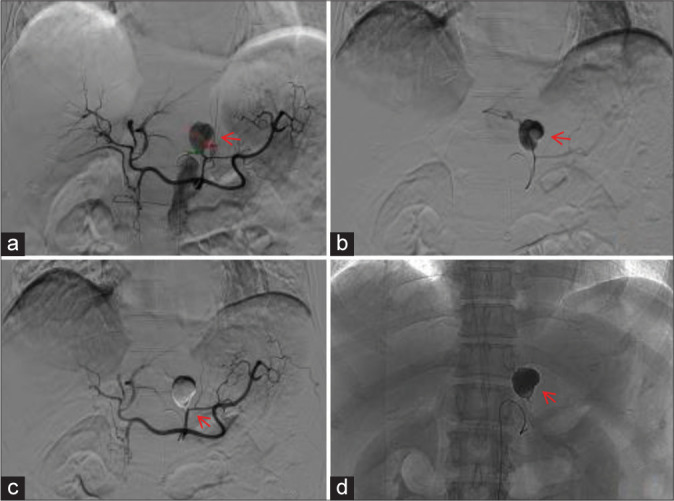

Results: A total of 32 pseudoaneurysms were embolized in 31 patients with peripheral pseudoaneurysms. All pseudoaneurysms originated from visceral arteries. Among them, 29 pseudoaneurysms were embolized with medical adhesive alone, and three pseudoaneurysms were embolized with coil-assisted medical adhesive. After endovascular embolization with medical adhesive, all pseudoaneurysms were successfully embolized. Technical success was 100%. All patients experienced cessation of bleeding after endovascular embolization with medical adhesive, and there were no serious post-operative complications. Clinical success was 100%. During the follow-up period, two patients experienced recurrent bleeding but no pseudoaneurysm recurrence was observed.

Abstract Image